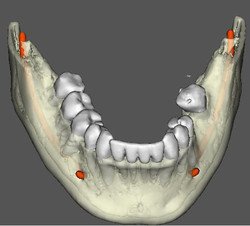

CIRURGIA GUIADA

REFORMATAÇÃO COM DENTALSLICE

Para trabalhar no DentalSlice basta solicitar na Clinica Serraro a tomografia computadorizada, onde as imagens DICOM (arquivos da tomografia) serão convertidas para o ambiente DentalSlice criando um arquivo que será enviado para o cirurgião dentista.

O Dental Slice é uma ferramenta de planejamento implantodôntico pré-operatório, desenhado para oferecer auxílio cirúrgico-protético com alto nível de precisão e aumentar a margem de segurança no tratamento.

O programa foi projetado para rodar em computadores pessoais e ambiente Windows.

O programa é acessível a qualquer cirurgião dentista e permite que o planejamento seja realizado pela própria equipe que vai realizar a cirurgia. As imagens também podem ser segmentadas, oferecendo melhor visualização de detalhes, como por exemplo do seio maxilar, canal da mandíbula ou de lesões.

• Tipos de Conversões do DentalSlice

O Dentalslice pode ser solicitado na Clinica Serraro de várias formas:

Tamanho da Conversão

Conversão simples

Limpeza de artefatos

Dentes Separados

Subtração de Dentes

Subtração de Prótese